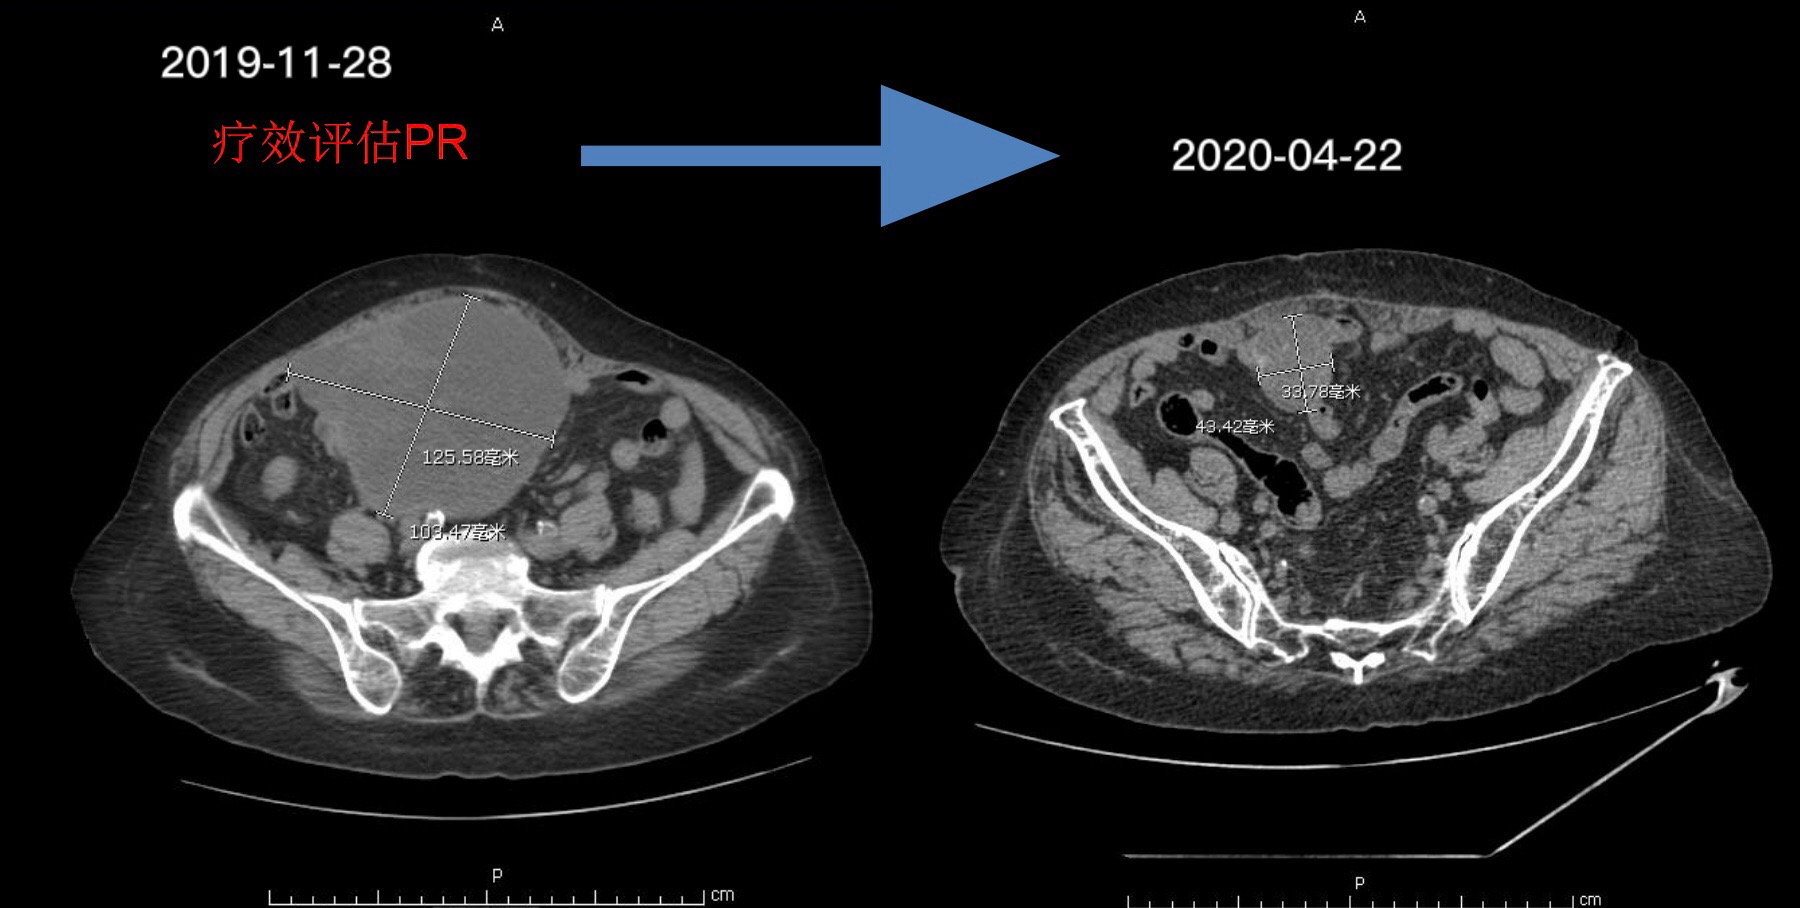

由于新型冠状病毒疫情影响,奶奶在放疗结束后4月来院复查,

包块较前明显缩小。疗效评估PR。(图为盆腔CT可见最大包块)